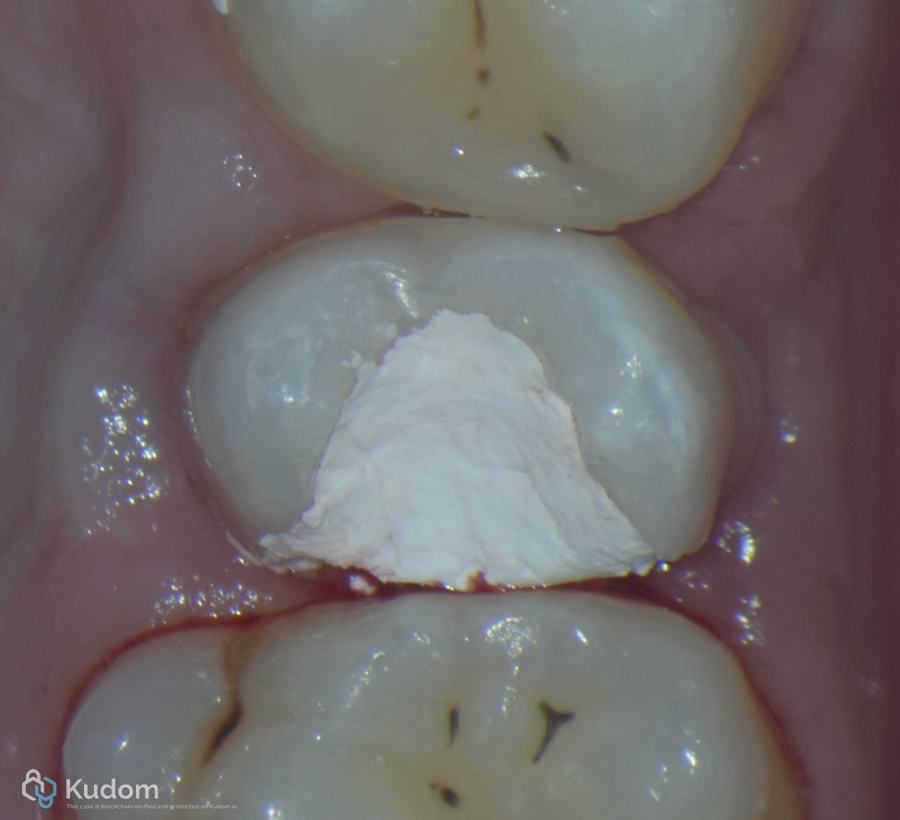

Fig. 3

Clinical view for upper 2nd Premolar with bad restoration